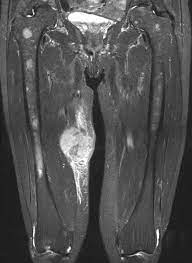

A patient mit schmerzloser weichteilschwellung am linken oberschenkel (markiert mittels kreuz) seit wenigen monaten. Lipome müssen nicht unbedingt behandelt werden. Danach heilt das ganze wieder nach 5 bis 6 tagen ab. Bei größeren tumoren muss häufig eine kompartimentresektion vorgenommen werden, d.h. Besonders lästig ist es allerdings, wenn sich großes lipom an der innenseite des oberschenkels gebildet hat.

Die ultraschallgesteuerte biopsie erbrachte die diagnose eines myxoiden liposarkoms. Das ‚ding' ist wie unschwer zu erkennen außen sehr rot und innen sehr warm. Die behandlung ist immer gleich: Wenn krebs mit einer schwellung beginnt. Wenn sie nicht von selbst verschwinden, desinfiziere ich die stelle und steche die dinger selbst auf. Meist tritt er durch einen sturz oder unfall auf. Danach heilt das ganze wieder nach 5 bis 6 tagen ab. Über 70 prozent sind in den armen und beinen lokalisiert, hierbei wiederum die meisten im bereich des oberschenkelknochens (abb.1). Aber die tumore sind bösartig, ärzte können sie nur mit. Erkennen ob du ein lipom hast. Der knochen des oberschenkels unterliegt einer zunehmenden entkalkung und verliert seine funktion. Ein lipom ist ein knubbel unter der haut, der überall am körper auftreten kann. Die behandelt man am besten mit schwarzer zugsalbe.